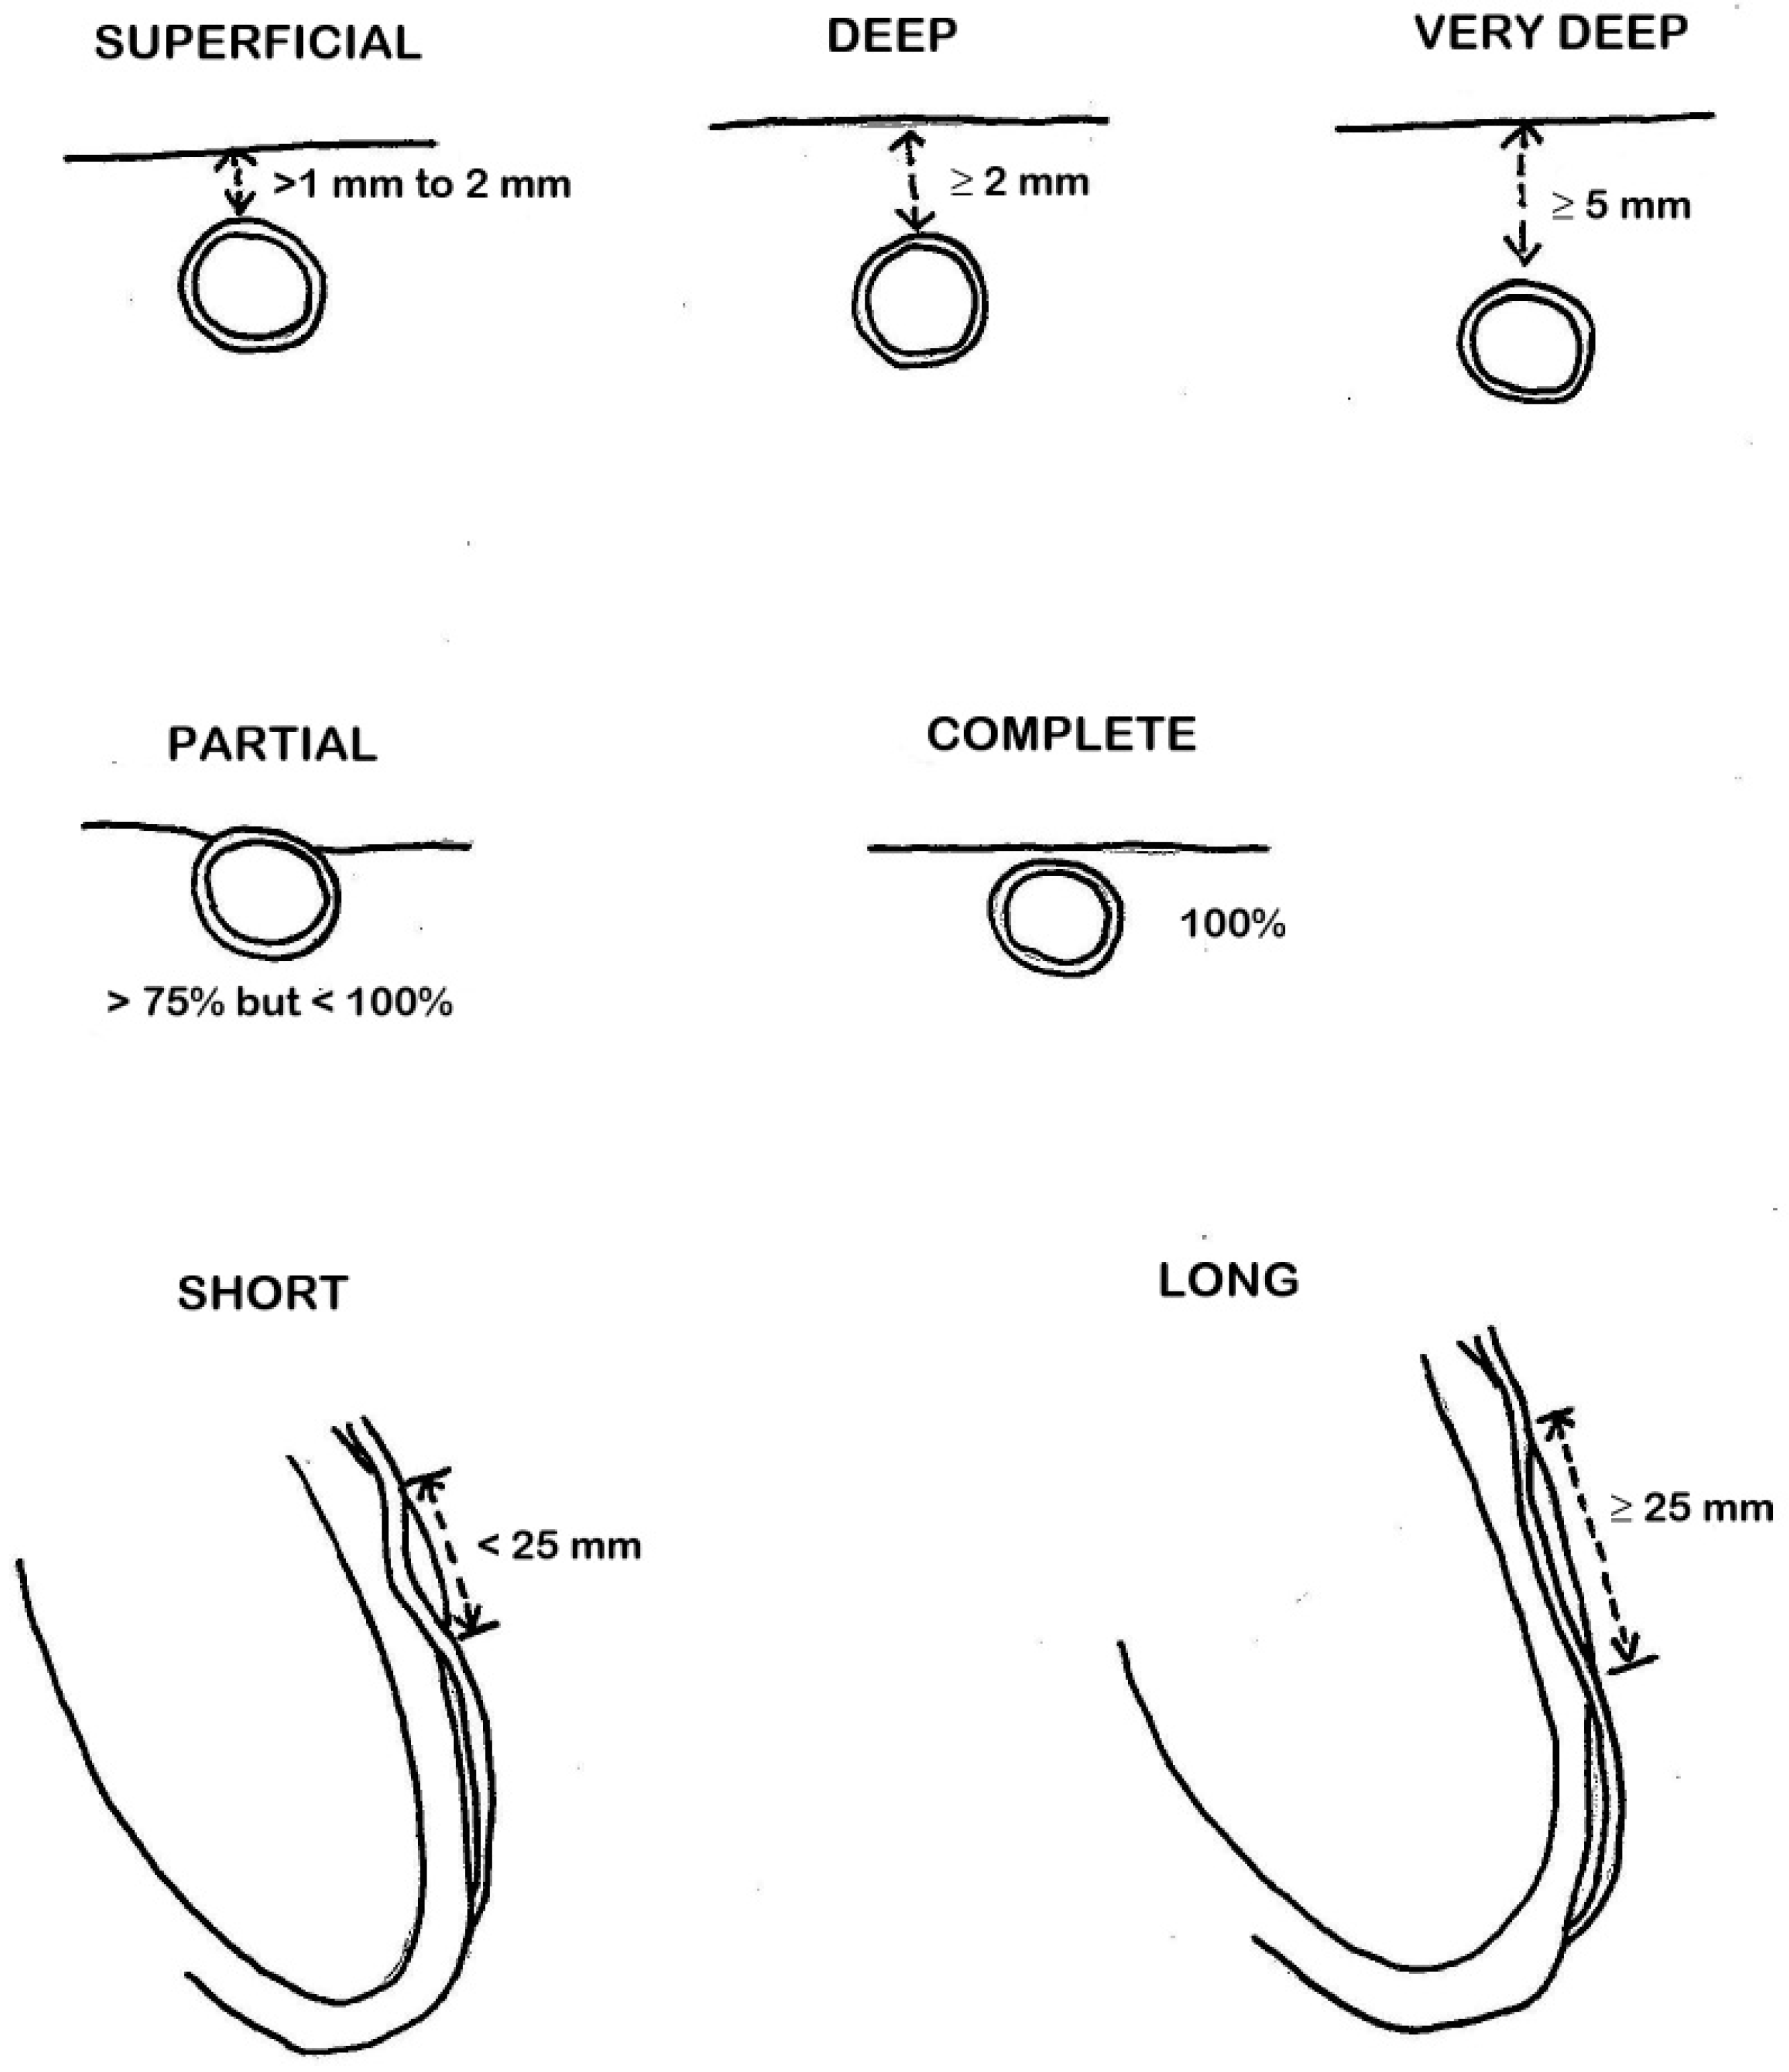

3. Role of CCTA: Anatomical Evaluation